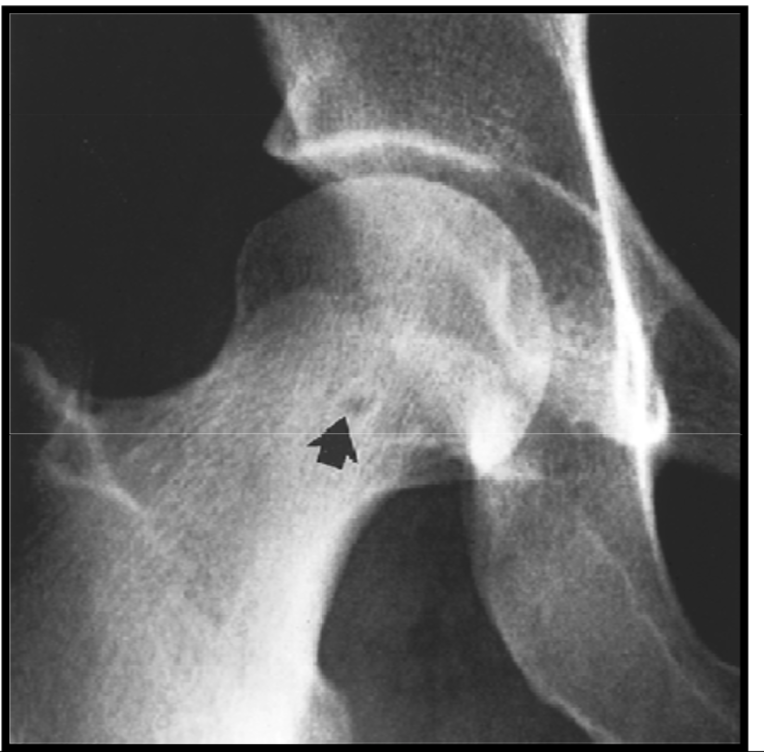

Synovial herniation pit or Pitt’s pit

variation anat normal